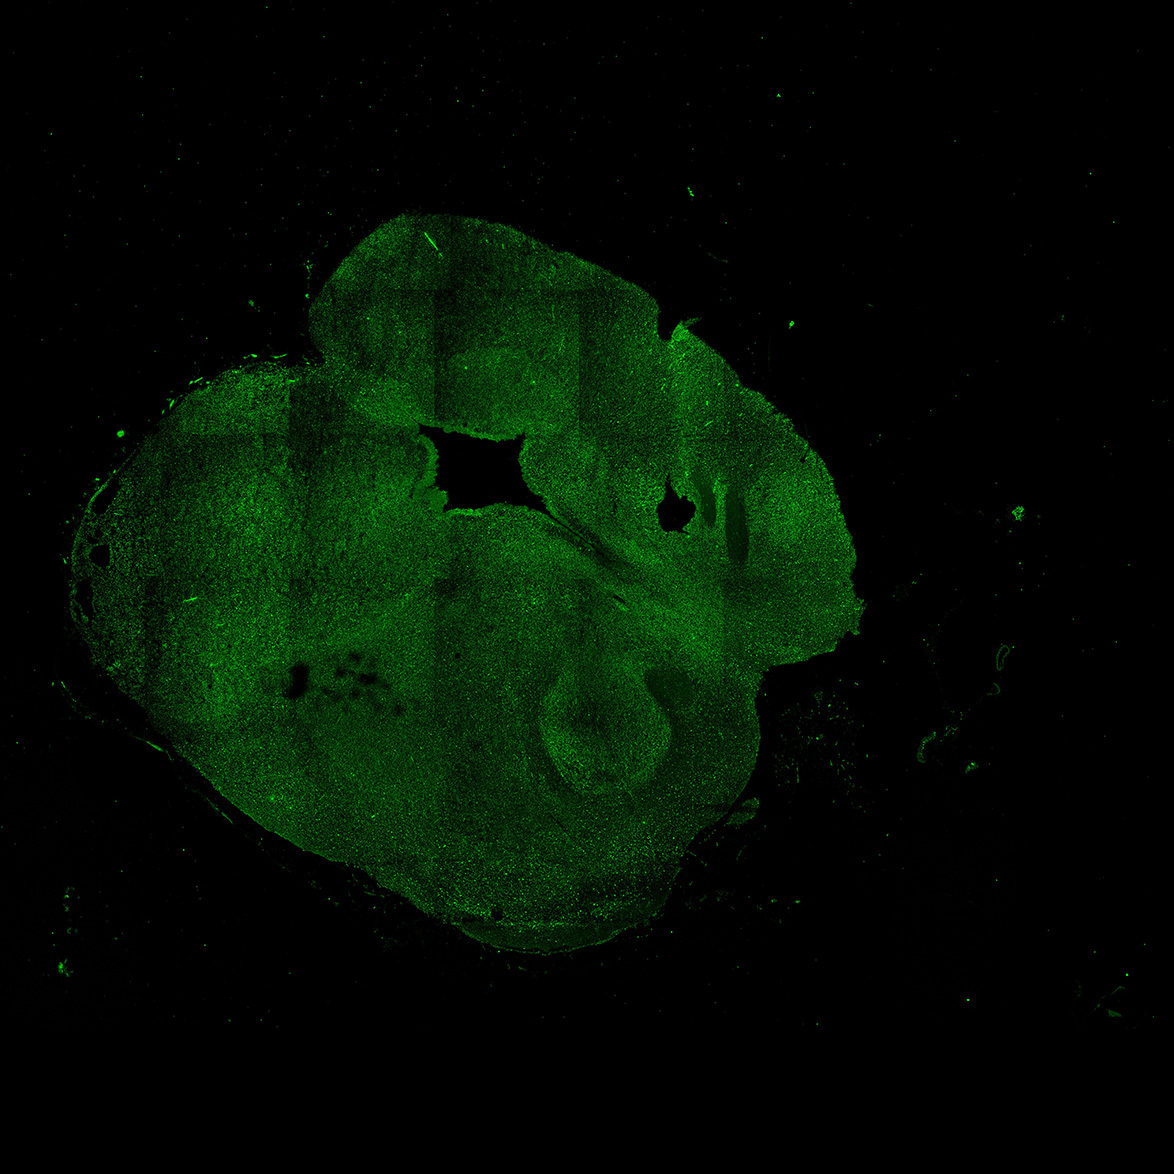

An anatomical analysis of the developing human midbrain from 6 post-conceptional weeks (PCW) to 22 PCW reveals increased tissue complexity, characterized by the emergence of dopaminergic nuclei, as highlighted by immunofluorescence analysis for tyrosine hydroxylase (TH).

11PCW

DAPI

11PCW human midbrain

MAP2

SOX2

Merged

TH